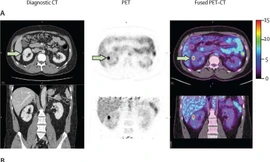

TPO - Một nghiên cứu mới do các nhà điều tra từ Trung tâm Ung thư Toàn diện Jonsson của UCLA Health (Mỹ), dẫn đầu đã chứng minh một kỹ thuật chụp ảnh mới, không xâm lấn có thể phát hiện chính xác ung thư biểu mô tế bào thận sáng, dạng ung thư thận phổ biến nhất.